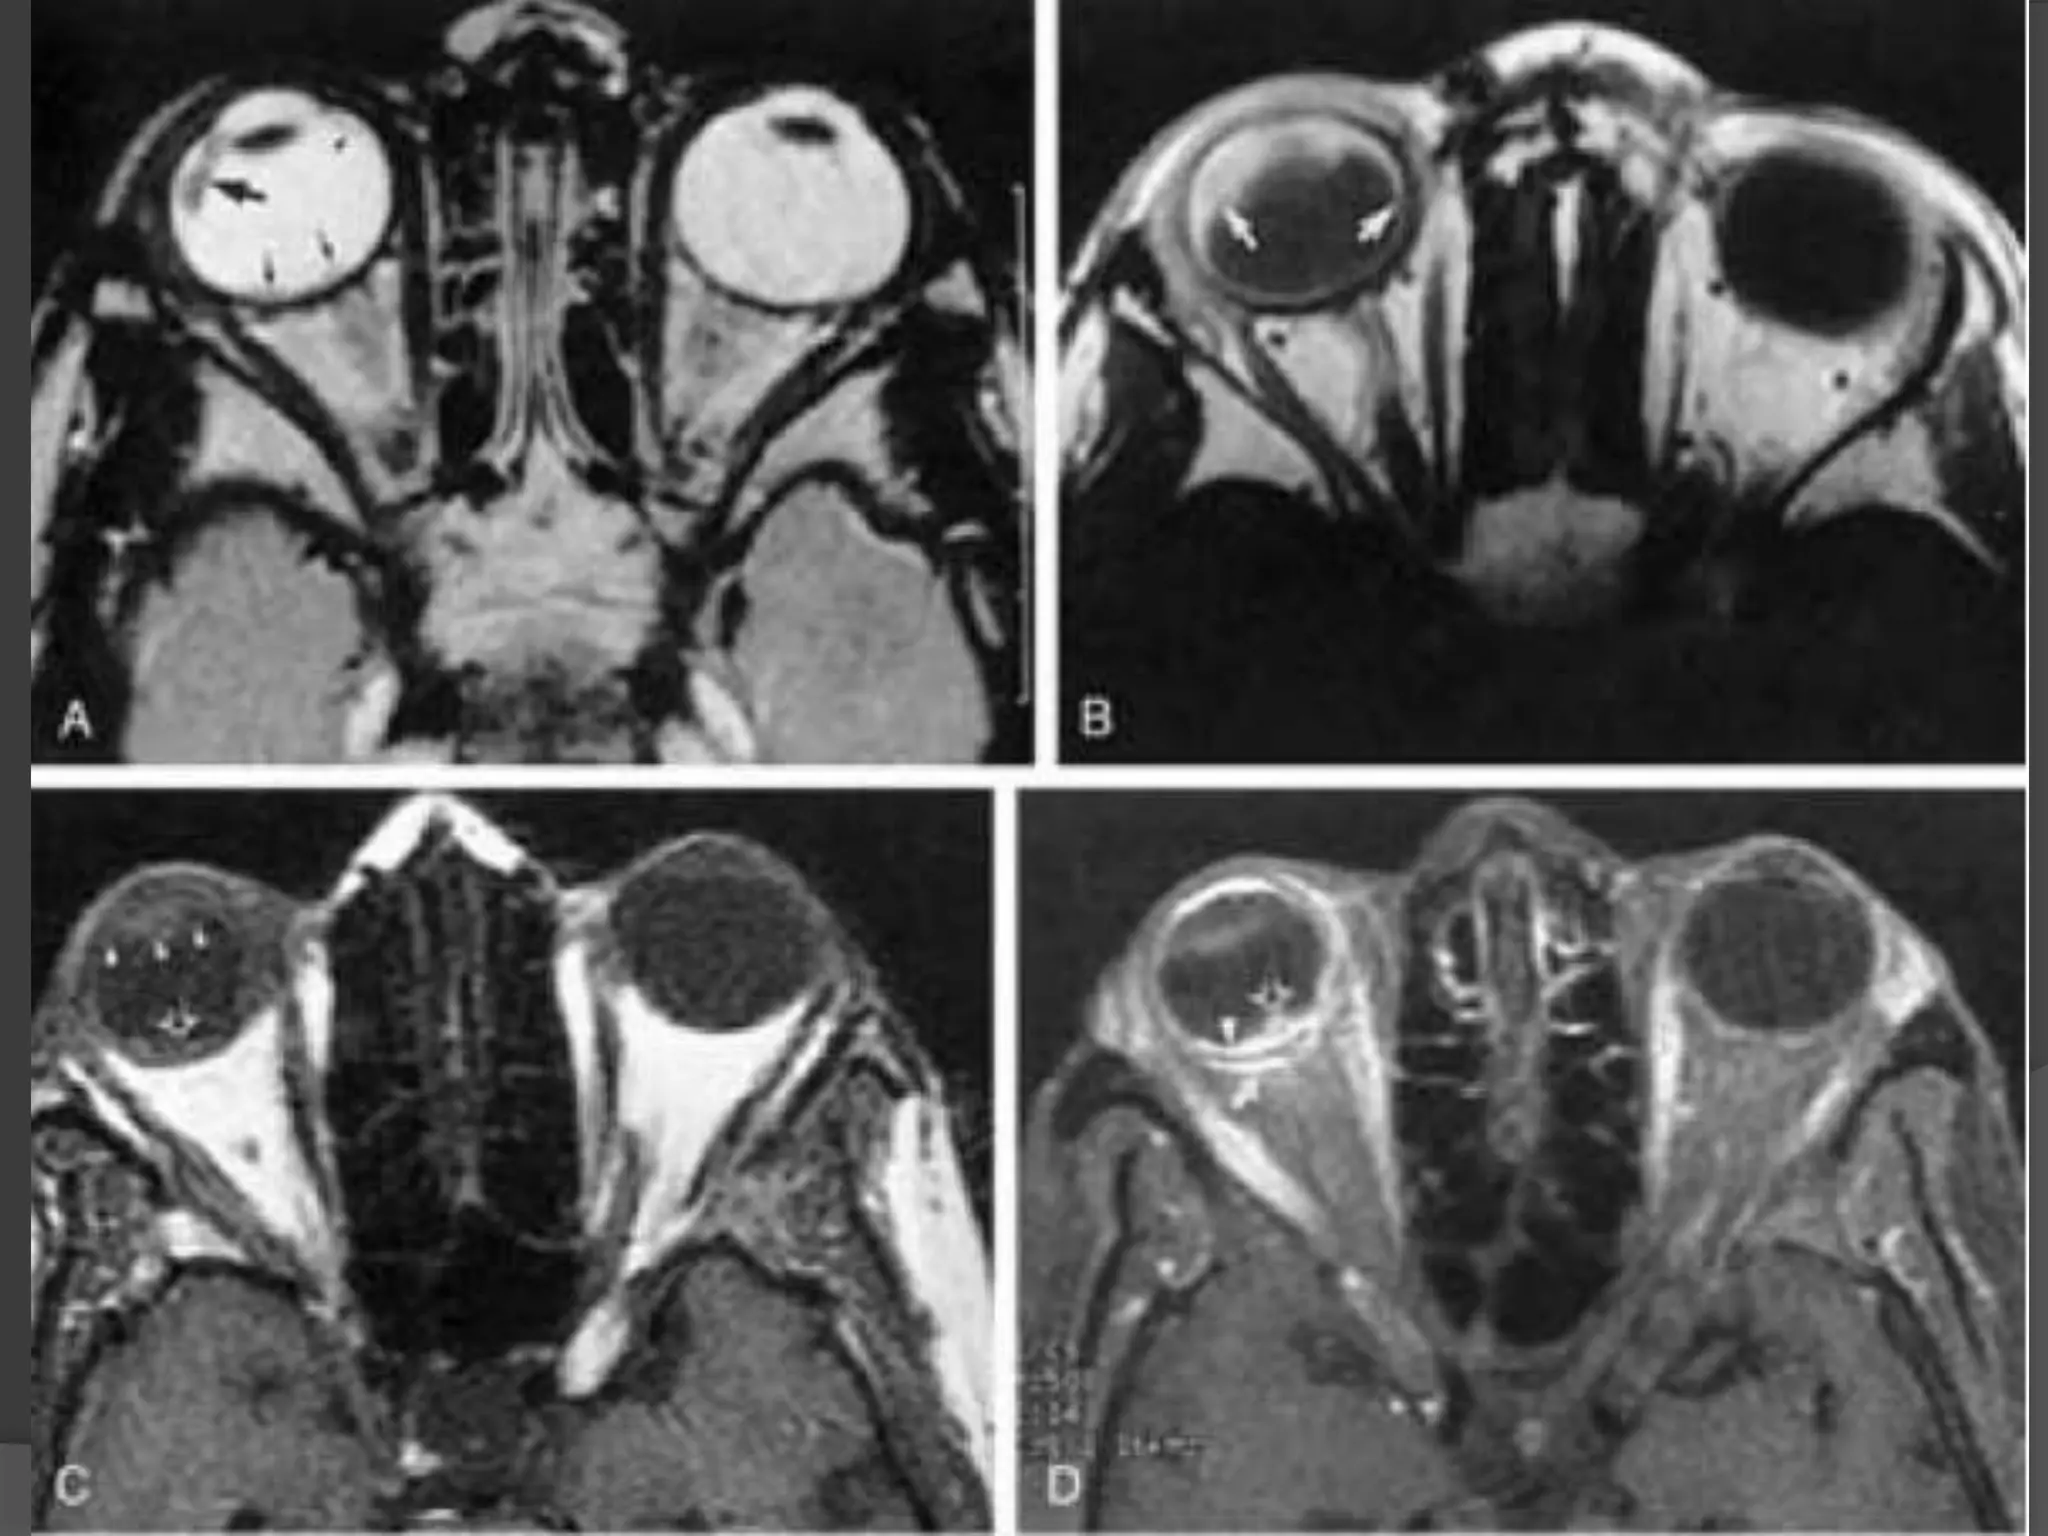

• #21 Granulomatous uveitis. A, Axial T2WI shows hypointense lesions (arrows). B, Axial enhanced, T1WI shows marked enhancement of the entire uveal tract (arrow). C, Unenhanced axial T1-WI shows nodular thickening of the posterior aspect of the right globe (arrow) and thickening of the anterior segment (arrowheads) of the right globe. D, Enhanced axial fat-suppressed, T1WI shows nodular enhancement of the posterior aspect of the right globe (arrowhead and open arrow) related to granulomatous involvement of the choroids.

• #22 Granulomatous uveitis. E, Enhanced sagittal T1WI shows granuloma at the optic disc (white arrowhead) as well as involvement of the optic nerve (black arrowhead ). F, Enhanced axial fat-suppressed, T1WI shows enhancement of the markedly thickened uveal tract (arrowheads).